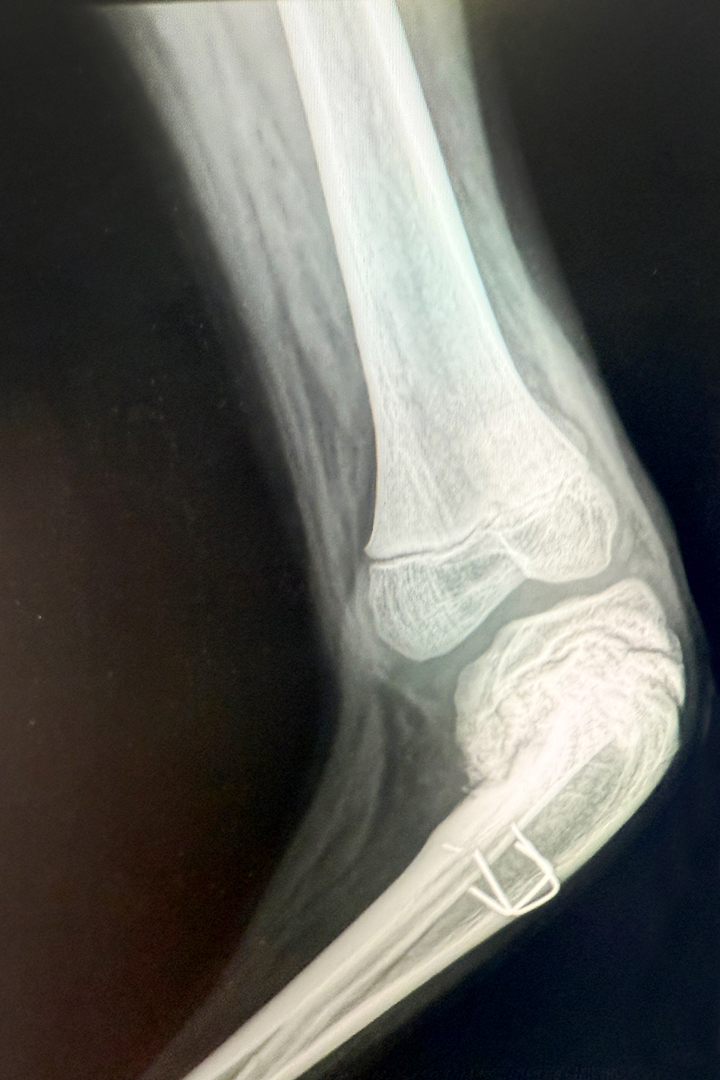

On his cell phone, Dr. Lundy has a photo of one of the patients he treated in Angola, a teenage boy with a severely deformed knee (varus deformity of his proximal tibia) causing his lower leg and foot to jut sharply to the side.

“I’ve been doing that stuff for decades,” Lundy said matter-of-factly about the kind of deformity that is relatively uncommon in the United States. During the boy’s operation, his knee was repaired and his lower leg reoriented, which will allow him to walk with a more normal gait.

Knee of a 14-year-old boy with a severe varus deformity of his proximal tibia Knee of a 14-year-old boy with a severe varus deformity of his proximal tibia.

Knee, post operationKnee, post operation.